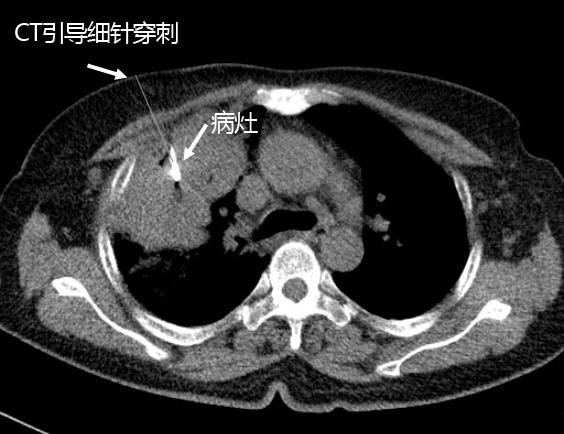

由于周圍型肺癌分型不同,治療方案不同。以往醫學界隻能在患者術後取腫瘤組織送病理檢查,才能确診其良惡性以及對腫瘤分型,即是先手術後确診。而經皮肺穿刺活檢術把診斷提到了前面,即先确診後治療,對周圍型肺腫瘤的診療無疑有重大意義。

由于周圍型肺癌分型不同,治療方案不同。以往醫學界隻能在患者術後取腫瘤組織送病理檢查,才能确診其良惡性以及對腫瘤分型,即是先手術後确診。而經皮肺穿刺活檢術把診斷提到了前面,即先确診後治療,對周圍型肺腫瘤的診療無疑有重大意義。